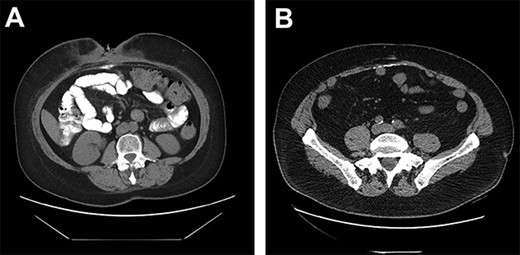

(A) DC misinterpreted as extra luminal contrast consistent with a fistula. (B) DC distributed horizontally along the hernia graft in a patient where CSAB were used.

Only two cases of DC in incisional hernia repair have been previously described, both involving polypropylene mesh [6–8]. Both these cases described the calcium deposited in a vertical manner along the linea alba. Although it is rare for DC to be clinically relevant, it has been estimated that some degree of calcinosis occurs in up to 25% of laparotomies, usually as a punctate deposit in the midline, or along suture points of the anterior or posterior rectus sheath [9]. In our series of 23 patients undergoing incisional hernia repair with porcine submucosa hernia graft and CSAB, 6 of the 11 patients (55%) who had a post-operative CT had evidence of DC occurring horizontally along the hernia graft insertion plane (Fig. 1B).